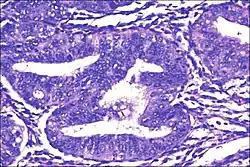

- Atypical endometrial hyperplasia (simple or complex) - Simple or complex architectural changes, with worrisome (atypical) changes in gland cells, including cell stratification, tufting, loss of nuclear polarity, enlarged nuclei, and an increase in mitotic activity. These changes are similar to those seen in true cancer cells, but atypical hyperplasia does not show invasion into the connective tissues, the defining characteristic of cancer. The previously mentioned study found that 22% of patients with atypical hyperplasia eventually developed cancer.[7]

Like other hyperplastic disorders, endometrial hyperplasia initially represents a physiological response of endometrial tissue to the growth-promoting actions of estrogen. However, the gland-forming cells of a hyperplastic endometrium may also undergo changes over time which predispose them to cancerous transformation. Several histopathology subtypes of endometrial hyperplasia are recognisable to the pathologist, with different therapeutic and prognostic implications.[4]